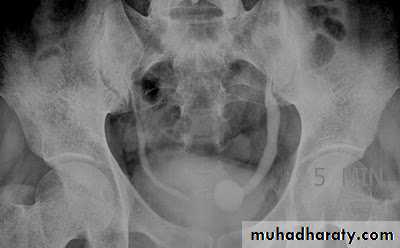

*Phlebolith (arrow):-round lucent centre,,it represents calcified thrombus in pelvic vein.